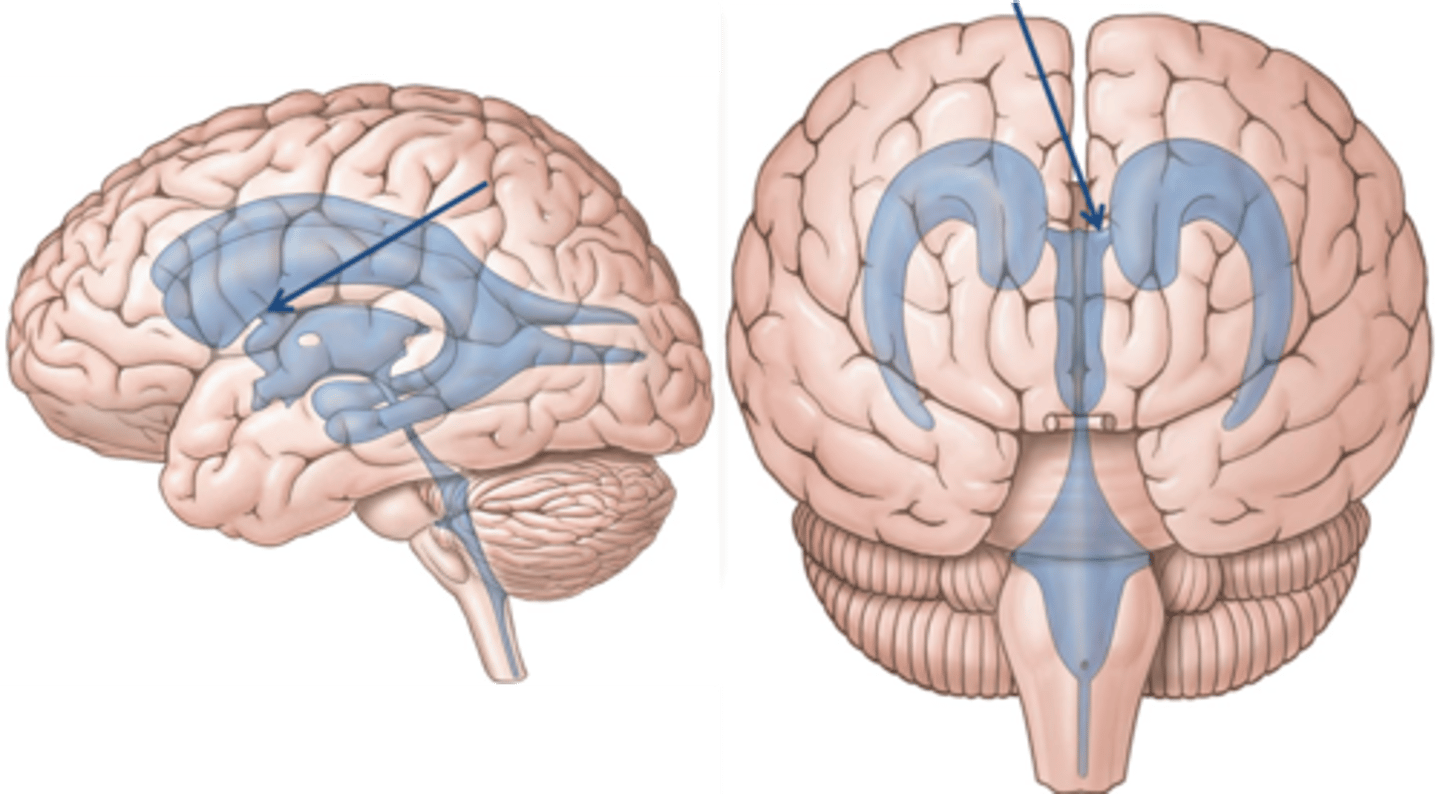

lateral ventricles

third ventricle

fourth ventricle

interventricular foramen

connects lateral ventricles to third ventricle

cerebral aqueduct

connects the third and fourth ventricles

choroid plexus

on the floor of all the ventricles, produces CSF

arachnoid villi